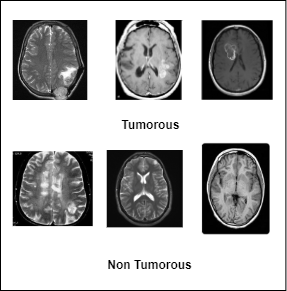

(b) A sample of the Kaggle dataset.

Figure 1: A sample of the Figshare and Kaggle dataset.

We have leveraged two publicly available datasets for conducting the study. The first dataset is the Figshare dataset [Cheng2017] that comprises 3064 T1-weighted brain tumor images from three classes. Collected from 233 patients, the slightly imbalanced dataset consisted of 708, 1426, and 930 images of meningiomas, gliomas, and pituitary tumors respectively. The images of that dataset are collected from three distinct viewpoints. The second dataset employed is commonly known as the Kaggle dataset [kaggle_brain_mri] which consists of 253 MRI images. 98 of those images are categorized as non tumorous while the rest of the images are tumorous. Unlike the Figshare dataset, the images of the Kaggle dataset are collected from one viewpoint. Figure 1 shows a sample of the datasets. In the data preprocessing stage, the dataset was first split into three non-overlapping training(70%), validation(10%), and test(20%) sets. The subsequent four steps are the region of interest (ROI) selection, adaptive histogram equalization, data augmentation, and resizing. The details of these processes are presented in Section 3.1.1, 3.1.2, 3.1.3, and 3.1.4 respectively. Figure 2 holds a diagrammatic overview of the preprocessing stage.